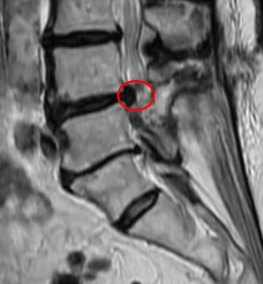

治療後

また術後の腰椎MRIで脊柱管狭窄症のあったL4/5の箇所が減圧されている所見を認めました。現在は、もともとあった右下肢の痛みと痺れ、腰痛はなくなり、「痛みを気にすることなく趣味の絵描きができるようになった」とお話しされていました。